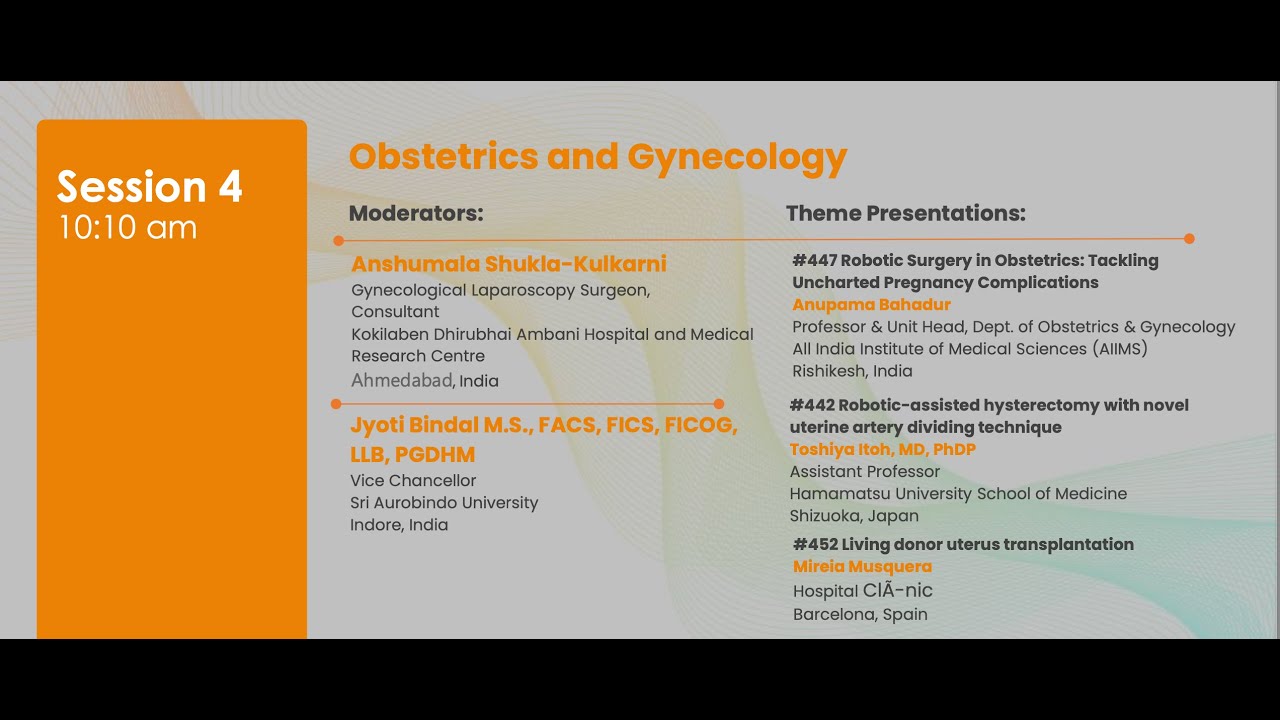

Jaipur Saturday Session 4 Obstetrics & Gynecology

Humans of Robotic Surgery, KS Awards, Robotics, Surgeon, Video Library ';